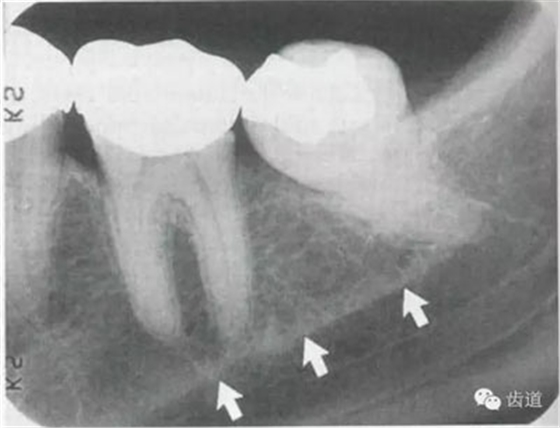

5)下頜管:

位于磨牙牙根尖下方,呈寬約為0.4cm凹面向下邊緣整齊的帶狀密度低的影像,其兩側(cè)有密度高的線條狀影像,為下頜管骨密質(zhì)